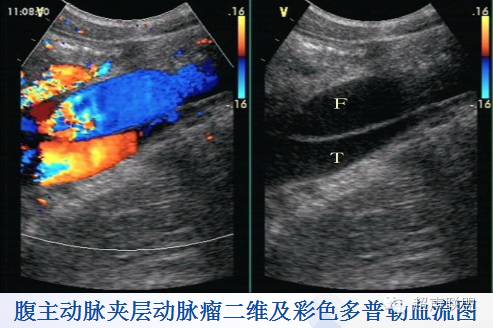

* 病理与声像图:真性动脉瘤,假性动脉瘤,夹层动脉瘤。

真性动脉瘤 | 假性动脉瘤 | |

病因 | 动脉硬化、感染致主动脉瘤样扩张 | 多为外伤致动脉管壁破裂、感染、医源性 |

肿块部位与形态 | 沿动脉纵向分布,呈梭形、囊状、圆柱状 | 位于动脉的一侧或前后,呈囊性或不规则 |

瘤壁结构 | 可分辨动脉管壁三层结构,常有钙化斑块 | 无动脉管壁三层结构,常无钙化斑块 |

瘤壁破裂口 | 无 | 有 |

进口与出口 | 进口与出口分开 | 同一通道 |

双期双向血流 | 无 | 有,血流从同一瘤口进出 |